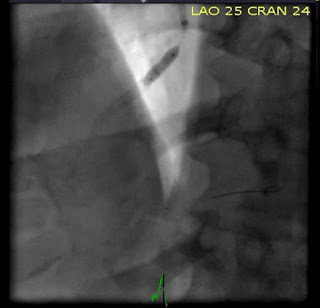

«Катетеризация выявила 100% окклюзию ПМЖВ, которая была успешно стентирована».